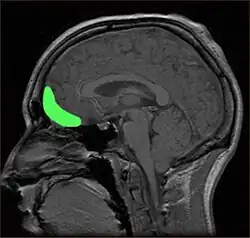

Approximate location of orbitofrontal cortex (OFC)

Within the brain, there is some support for the role of the orbitofrontal cortex (OFC) in producing self-conscious emotions, such as shame (Beer, et al., 2003; Leary, 2007; Sturm, Ascher, Miller, & Levenson, 2008). People with damage to the OFC have shown impairments in both the ability to appropriately express self-conscious emotions, such as shame, and in their social behaviour (Beer et al.). In Beer and colleagues' (2003) study, participants with OFC damage were more likely to overshare intimate information on a disclosure task, for example, telling about cheating on their partner, whereas other participants gave more guarded answers, such as being embarrassed when they did not understand a punchline. Those with OFC damage were also less likely to recognise self-conscious emotions on a recognition test than participants without any damage, although there was no difference between the groups in recognising other emotions (Beer et al.). This inability to correctly detect others' emotional responses suggests people with OFC damage may be missing important signals that their behaviour is inappropriate, such as others' embarrassment (Beer et al.). However, since others do not have to be real or physically present for a person to experience shame or the other self-conscious emotions, this suggests damage impairs the ability to correctly infer others' reactions to behaviour (Beer et al.).